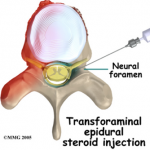

Transforaminal Injection

A transforaminal injection is an injection of long acting steroid into the opening at the side of the spine where a nerve roots exits. This opening is known as a foramen. There is a small sleeve of the epidural space that extends out over the nerve root for a short distance. This epidural root sleeve is just outside the spinal canal. Sometimes these injections are referred to as root sleeve blocks, root blocks or transforaminal epidural blocks.